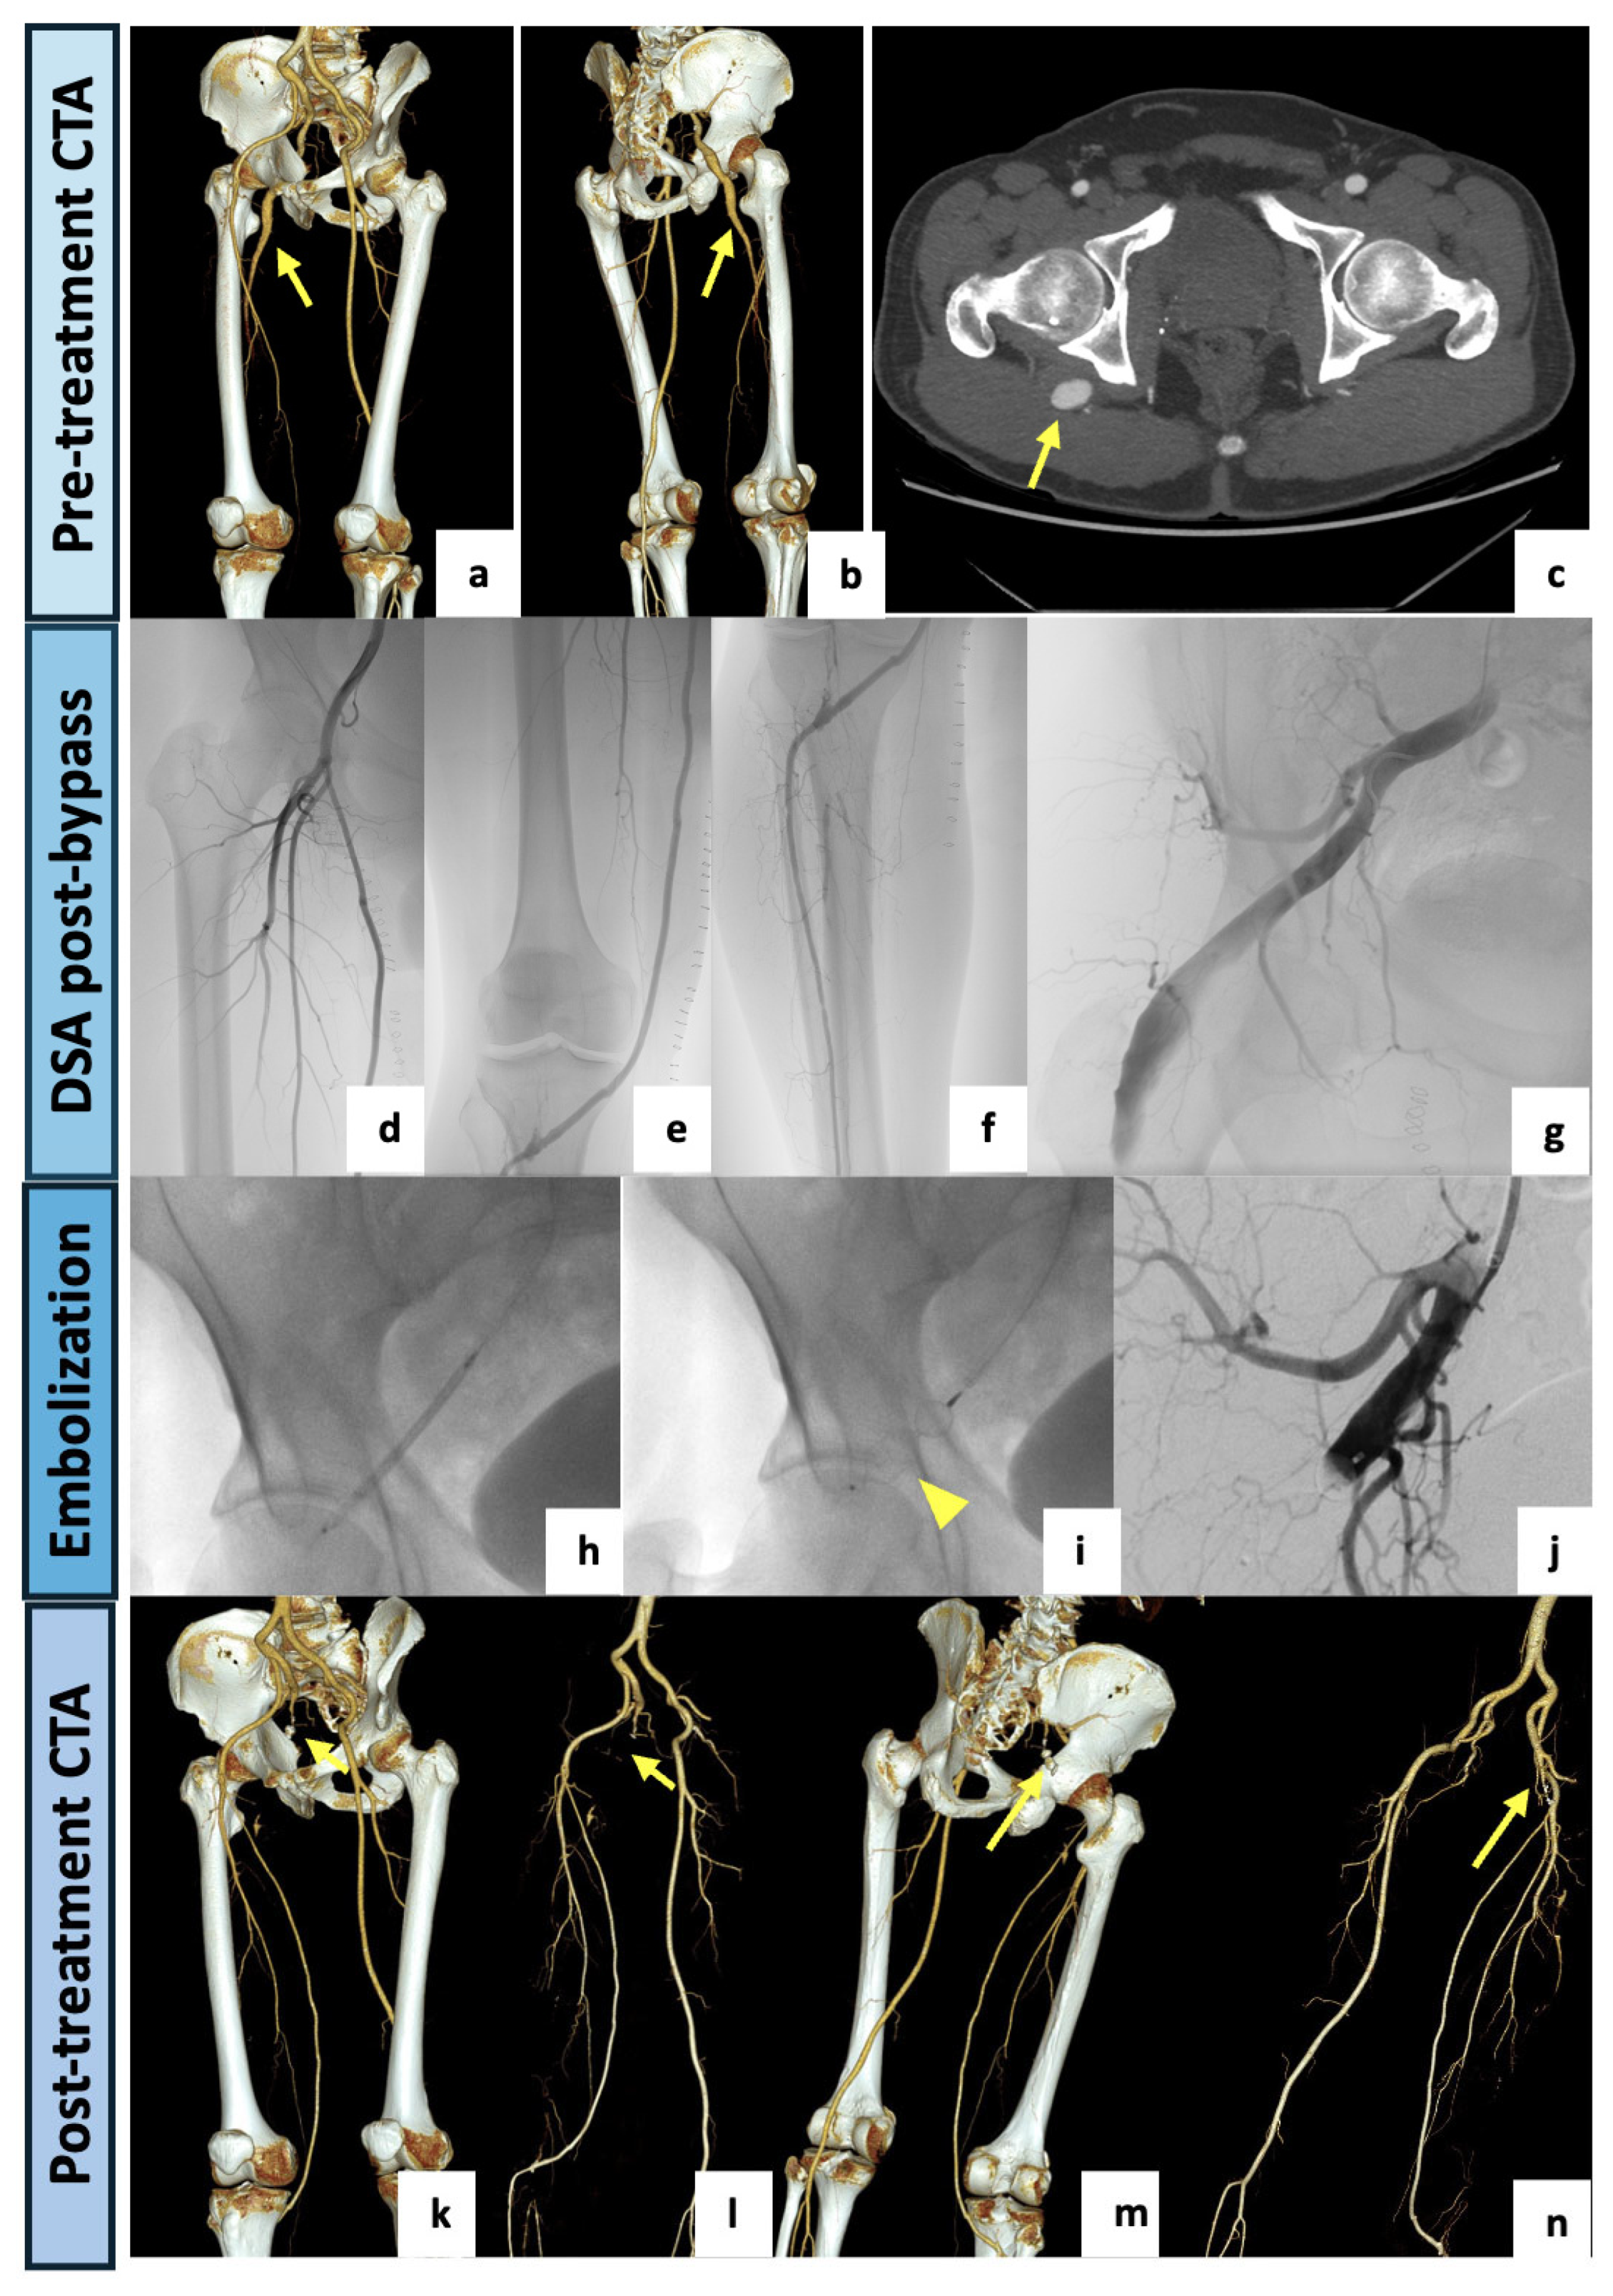

A 79-year-old woman was admitted to our hospital for intense right flank and buttock pain with a burning sensation in the gluteal region radiating down the back of her right lower limb and preventing her from walking normally. She had no significant medical history other than experiencing several similar episodes of pain. Physical examination revealed stable vital signs, palpable and symmetric femoral pulses, normal distal bilateral perfusion, no claudication or ulcers and no clinical signs of superficial or deep vein thrombosis. Neurological examination revealed no motor or sensory deficit. Blood tests on admission were unremarkable. At DUS examination of the lower limbs, a normal right common femoral–external iliac axis was detected, with a regular right ankle–brachial index. The left-limb DUS showed a regular common femoral–external iliac axis with a hypoplasic SFA and popliteal low flow pattern. The ankle–brachial index was bilaterally normal. A CTA examination (Figure 2) showed a right PSA originating from the internal iliac artery, running through the greater sciatic foramen, entering in the thigh and continuing as a popliteal artery, supplying the distal arteries of the leg. The PSA was associated with a normal SFA (type 1). An aneurysmal degeneration of the PSA, measuring 57 mm in the maximal caliber with poor mural thrombus, was found in the posterior aspect of the thigh. On the left limb, a fully developed and completely occluded PSA with a hypoplastic SFA (type 2A) was detected. The popliteal artery was supplied by collateral pathways originating from the hypoplastic SFA and the deep femoral axis. Having confirmed that the patient was not suffering from left lower limb claudication interfering with normal activities, the case was collegially discussed and evaluated as eligible for endovascular management of the right aneurysmatic PSA. The procedure was performed in our institutional angiosuite (flat-panel C-arm system, Artis zee, Siemens Healthcare, Erlangen, Germany). A right common femoral artery access was performed under local anesthesia (10 mL of Mepivacaine 2% solution) and a 6F-sheat (45 cm) introducer sheath was positioned. A left humeral access with a long 4F-sheat (60 cm) was also utilized for diagnostic angiographies. The left femoral access was avoided due to a focal chronic dissection in the left external iliac artery, as shown by the CTA. The right PSA was selectively catheterized, and the aneurysm was embolized with the “sandwich technique” to avoid retrograde recanalization. Two vascular plugs (AVP—Abbott Medical, North Plymouth, MN, USA) were deployed in the outflow (12 mm) and in the inflow vessel (14 mm). The final angiograms showed a nearly complete occlusion of the aneurysm (small residual slow flow). The procedure was successfully completed without complications. The patient was discharged after two days with single antiplatelet therapy. At the clinical follow-up, a complete disappearance of symptoms and no further need for pain medication were confirmed, and the 1-month CTA follow-up examination showed the complete exclusion of the PSA aneurysm.

Figure 2.

(a) VR reconstruction of the preoperative CTA showing a right PSA originating from the internal iliac artery (arrow), continuing as a popliteal artery and associated with a normal SFA (type 1). (b–f) Three-dimensional reconstructions, with and without bone structures, and axial maximal intensity projections showing a huge aneurysmal degeneration (57 mm in the AP caliber) of the PSA in the posterior aspect of the thigh (arrows). (g) Intraprocedural selective angiography of the right PSA performed after obtaining a left humeral access with a 4F-sheat (60 cm), confirming a large aneurysm. (h,i) Intraprocedural images obtained after right common femoral artery access with a 6F-sheat and right PSA selective catheterization. (j,k) Aneurysm exclusion with “sandwich technique”: embolization through two vascular plugs deployed in the outflow and in the inflow vessel (arrowheads). (l) At final angiography, a nearly complete occlusion of the aneurysm (small residual slow flow) was documented. (m–p) VR reconstruction of postoperative CTA (1-month), demonstrating the complete exclusion of the PSA aneurysm. Both inflow and outflow were occluded by vascular plugs (arrows).